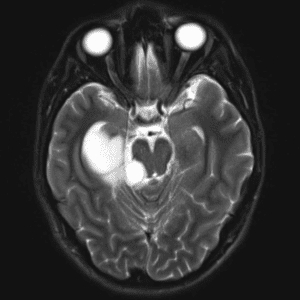

Case #42

Giant cerebral aneurysm